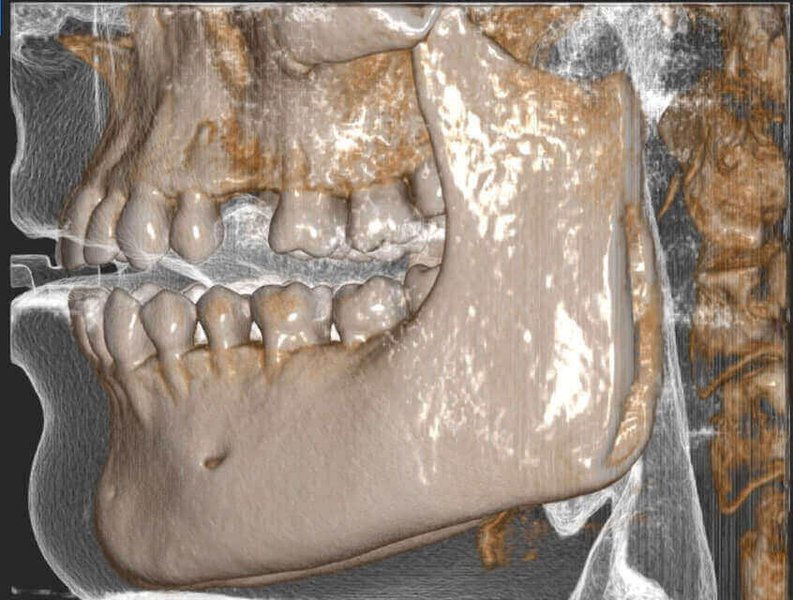

КОМПЛЕКСНЫЙ ГИБРИДНЫЙ КЛКТ ДЛЯ 2D/3D ВИЗУАЛИЗАЦИИ. ИЗОБРАЖЕНИЯ В ВЫСОКОМ РАЗРЕШЕНИИ С ЗАХВАТОМ МЕЛЬЧАЙШИХ ДЕТАЛЕЙ

GIANO HR – универсальное обновляемое устройство от NewTom для всех задач, связанных с радиографией. Благодаря полному диапазону опций 2D и 3D исследования для стоматологии оно предлагает множество особых трехмерных обследований для челюстно-лицевой хирургии, оториноларингологии и осмотра шейного отдела позвоночника. Визуализация только наивысшего качества с технологиями и опытом NewTom

NNT – программное обеспечение NewTom, предоставляющее несколько специальных режимов применения для имплантологии, эндодонтии, пародонтологии, челюстно-лицевой хирургии и радиографии. Это мощное технологически новейшее устройство, разработанное, чтобы снимать и обрабатывать изображения в несколько простых шагов для получения информации, необходимой для конкретного подробного диагноза пациенту. Продвинутое устройство, дающее врачу специальные инструменты для измерения анатомической области (расстояния и углы), нахождения нижнего альвеолярного нерва и замера объема верхних дыхательных путей.

NewTom GiANO HR новейшая модель была официально представлена на международном конгрессе радиологов ECR 2018 в марте в Вене. Благодаря обновленным системам механики и запатентованным механизмам работы аппарат отличается от своих сверстников Высочайшим качеством получаемых изображений, как 2D, так и 3D. Лучшее качество снимков и мы отвечаем за это! Этот аппарат заменит три аппарата! Панорамный аппарат, цефалометрическая приставка и конусно-лучевая компьютерная томография интегрированы в единую платформу. В комплекте детектор для выполнения 3D исследований с захватом области 13х16 см, Сьемный 2D CMOS детектор для выполнения панорамных исследований, и ТРГ.